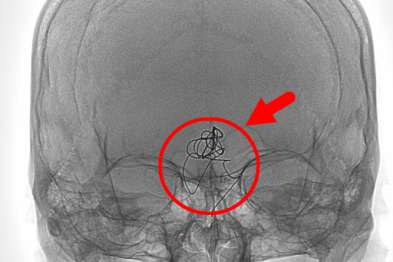

介入微创打通肾动脉,患者告别顽固性高血压